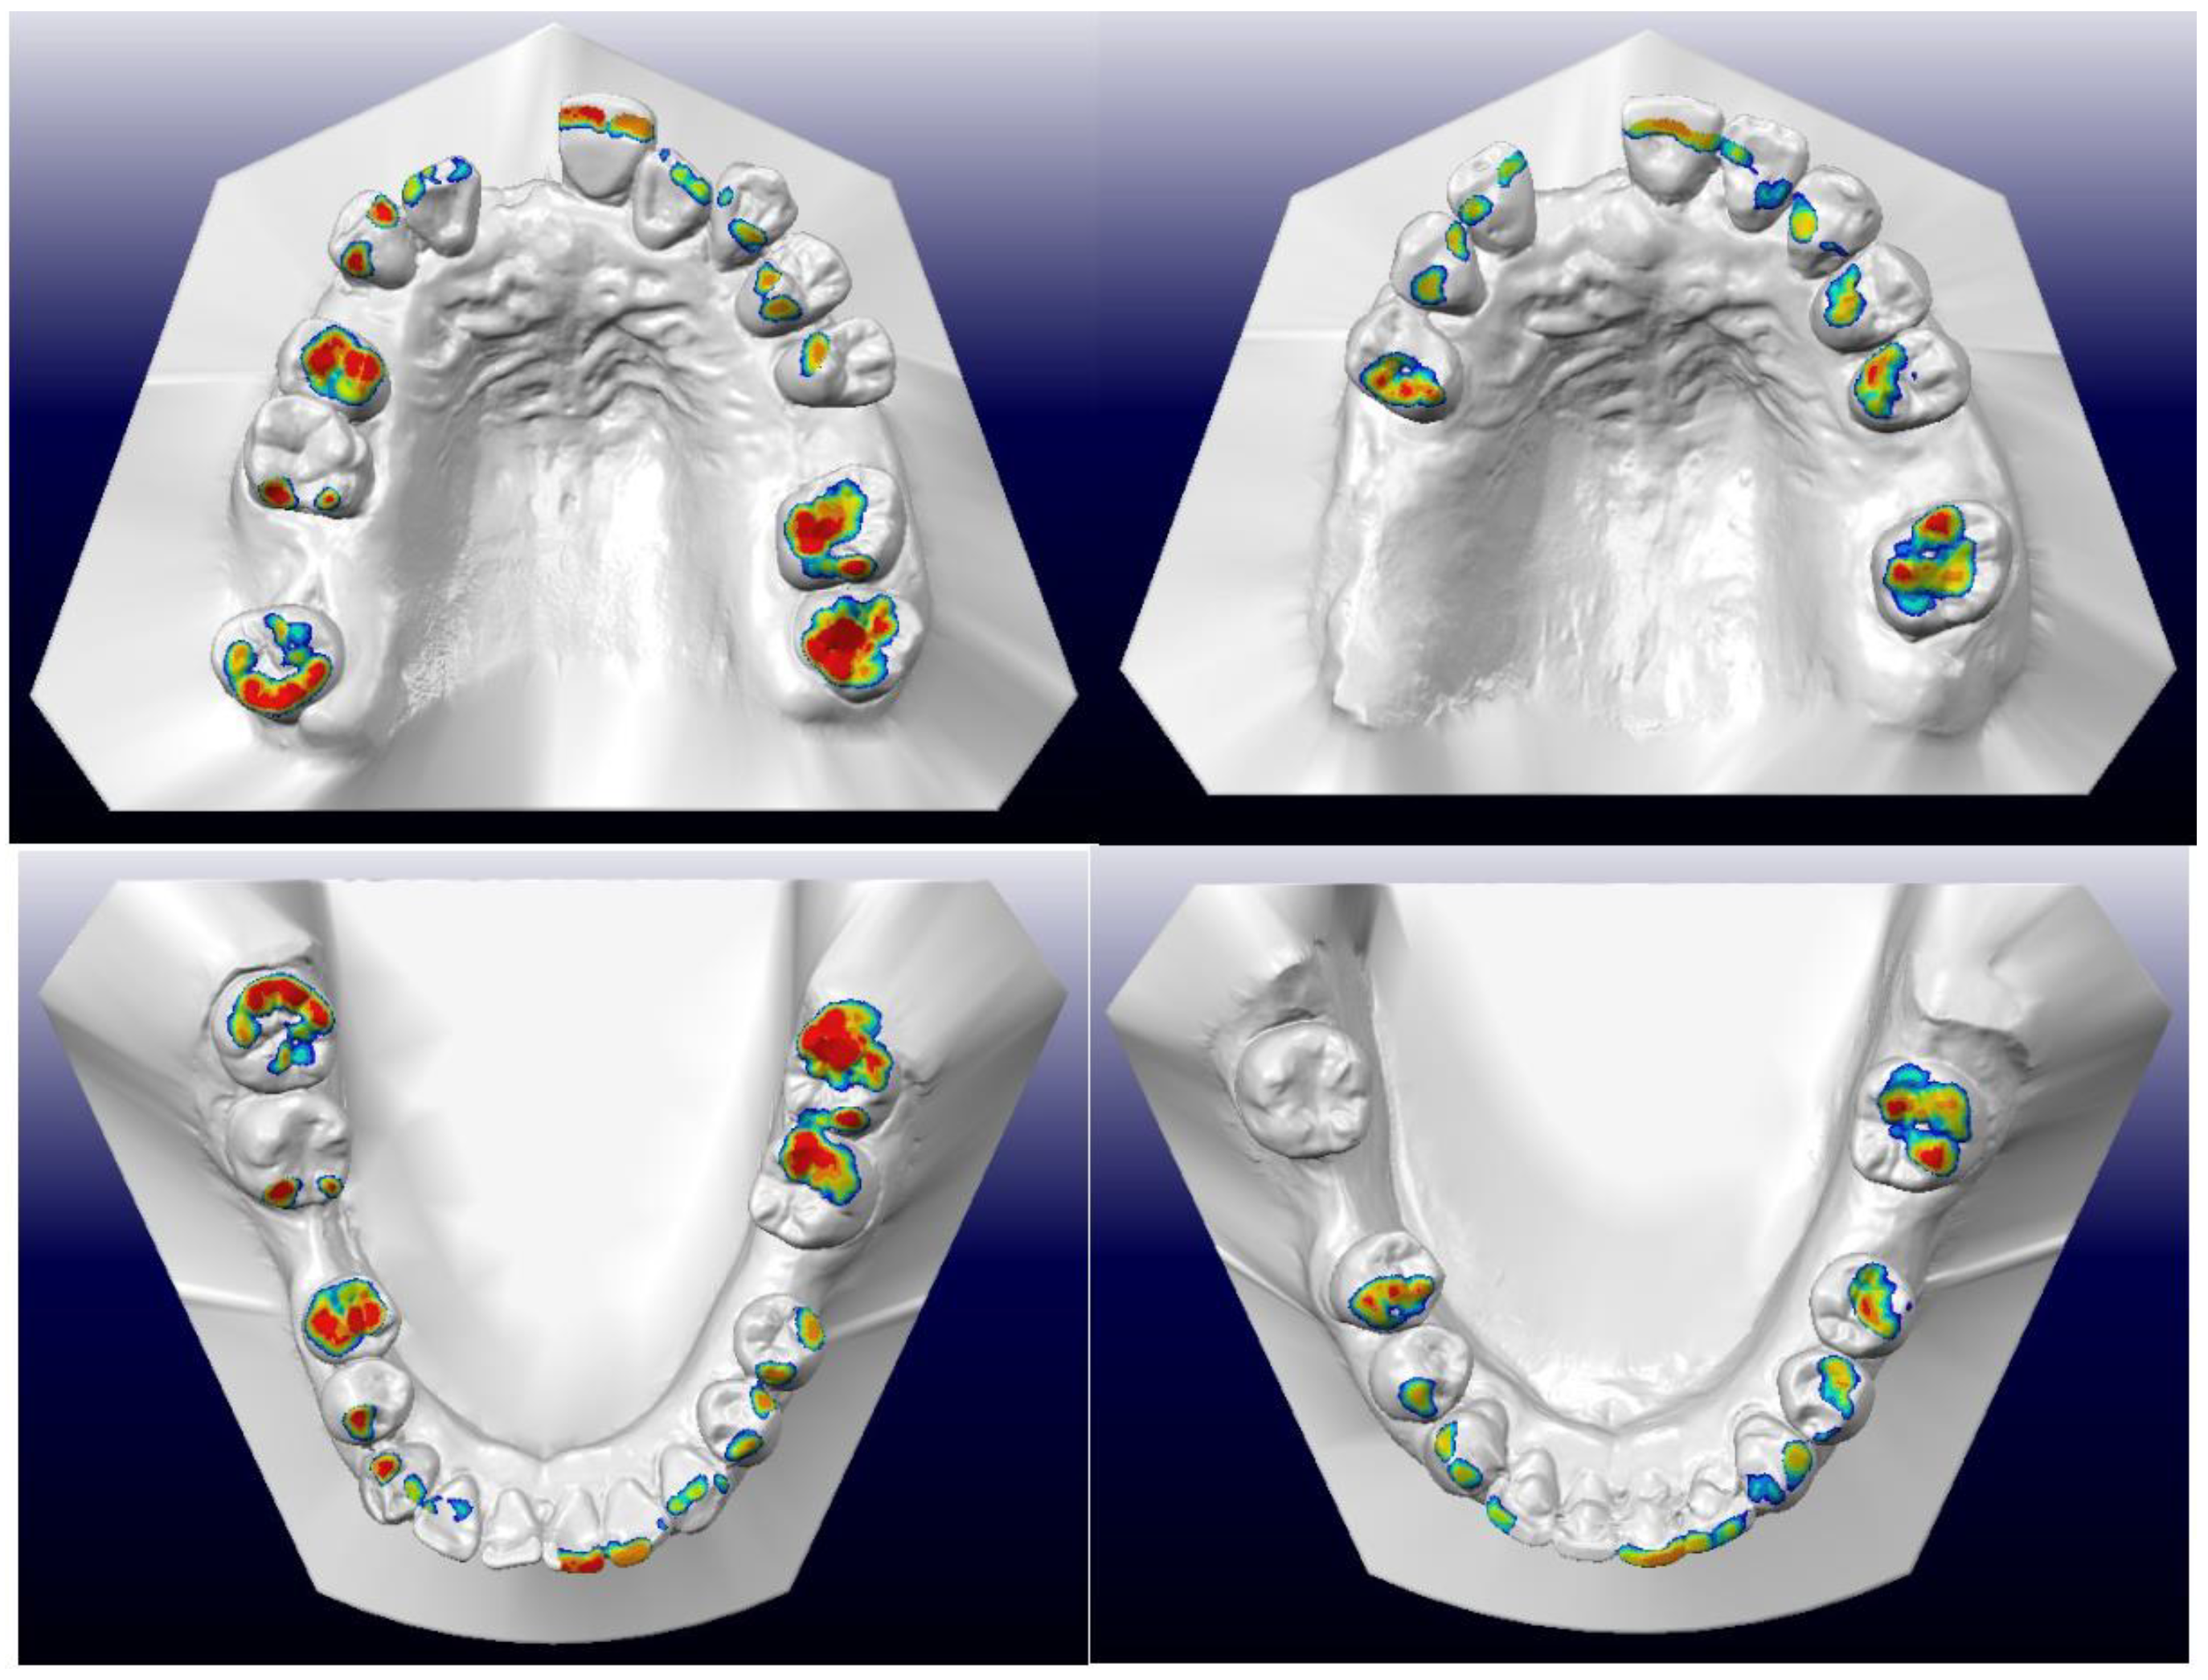

- During the treatment of this patient with Stage IV Grade C generalised periodontitis, we addressed the biomechanical challenges outlined in lists 3.1 to 3.3 at four specific time points.

- (3.4.1)

- As teeth 24 and 25 were significantly buccally displaced, sectional cantilever mechanics were used rather than direct bonding of the entire upper arch. There were two reasons for this. The first reason was to avoid creating unfavourable force systems on the other teeth due to the buccally displaced positions of teeth 24 and 25. Bonding brackets onto all upper teeth and engaging them with a straight wire could have resulted in an abnormal or skewed arch form. The second reason was that tooth 16 had a poor prognosis and was to be extracted in the future. Therefore, we decided to use tooth 16 as free anchorage to bring teeth 24 and 25 into the planned archform with cantilever mechanics, before proceeding with straight wire mechanics.

- (3.4.2)

- During the alignment and levelling stage, tooth 35’s crown was displaced distally and rotated disto-bucally, so a box loop capable of delivering the desired magnitude of force and precisely regulating the force direction was used. The box loop increased the total amount of wire between brackets of teeth 34 and 35, which produced a reduced load–deflection ratio and a greater range of action than any other loop type [41]. Furthermore, as the box loop was composed of a series of vertical and horizontal levers contoured to provide a short section of archwire that was freely movable in all planes in which it was activated, we used it to tip the crown of tooth 35 mesially and rotate tooth 35 mesio-lingually [41]. Moreover, sufficient anchorage was provided by the relatively rigid, continuous wire portion adjacent to the box loop, spanning from teeth 34 to 45, which effectively differentiated the active and reactive units.

- (3.4.3)

- As discussed in list 3.3, periodontally compromised teeth would tip excessively in response to orthodontic force which is applied at the regular bracket level. Therefore, if the aim is to achieve bodily retraction of incisors, it is best to bond the brackets as cervically as possible. However, since the pre-treatment upper and lower incisors were proclined, we aimed to achieve ‘uncontrolled tipping’ during retraction, and thus, the brackets were bonded at the regular positions on the upper and lower incisors [42].

- (3.4.4)

- The attempted placement of mini-screws on the upper alveolar bone resulted in dislodgement due to the low sinus floor. This was caused by sinus peumatization which was a continuous physiological process that increased the volume of the paranasal sinuses [43]. To address this, lower buccal shelf mini-screws were used instead to retract the upper arch with Class I elastics.